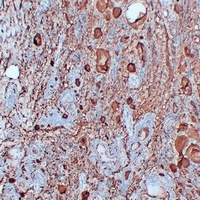

Immunohistochemical analysis of Thyroglobulin staining in human papillary thyroid carcinoma formalin fixed paraffin embedded tissue section. The section was pre-treated using heat mediated antigen retrieval with sodium citrate buffer (pH 6.0). The section was then incubated with the antibody at room temperature and detected using an HRP conjugated compact polymer system. DAB was used as the chromogen. The section was then counterstained with haematoxylin and mounted with DPX.

Immunohistochemical analysis of Thyroglobulin staining in human thyroid follicular carcinoma formalin fixed paraffin embedded tissue section. The section was pre-treated using heat mediated antigen retrieval with sodium citrate buffer (pH 6.0). The section was then incubated with the antibody at room temperature and detected using an HRP conjugated compact polymer system. DAB was used as the chromogen. The section was then counterstained with haematoxylin and mounted with DPX.